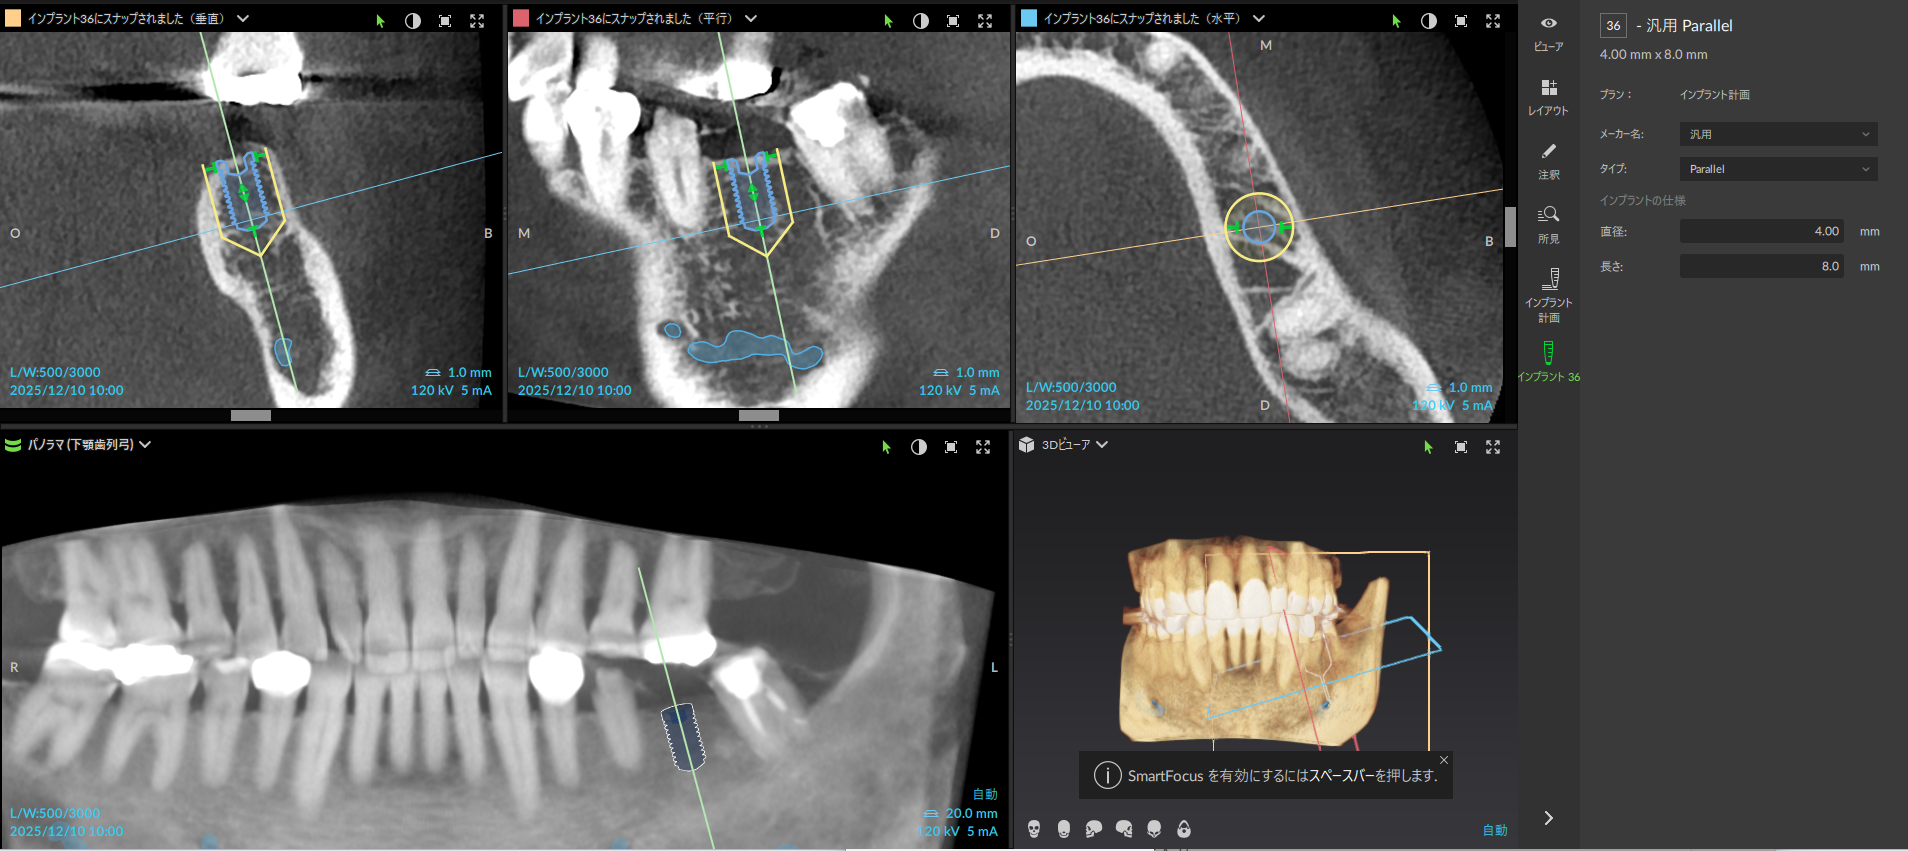

安心で低被ばくのCT撮影

骨の状態を確認するためのCT撮影

低被ばくで部分的な撮影も可能

追加で撮影が必要な場合も追加料金がなく必要に応じて撮影させていただきます。

撮影歯科用CTによる「3次元立体診断」

コンピューター上での「シミュレーション手術」

従来のレントゲン(2次元)だけでは、骨の厚みや奥行き、神経や血管の正確な位置までは把握できません。 当院では、歯科用CT(3次元)撮影を必須としています。骨の形、硬さ、神経までの距離を0.1ミリ単位で立体的に解析し、手術のリスクを極限まで排除します。 ※被ばく量の少ない最新機種を導入しています。

CTデータを専用のシミュレーションソフトに取り込み、コンピューター上で仮想手術を行います。 「どの位置に、どの角度で、どの深さに、どのサイズのインプラントを埋めるのがベストか」を事前に設計します。これにより、実際の手術時間を短縮し、お体への負担を軽減します。